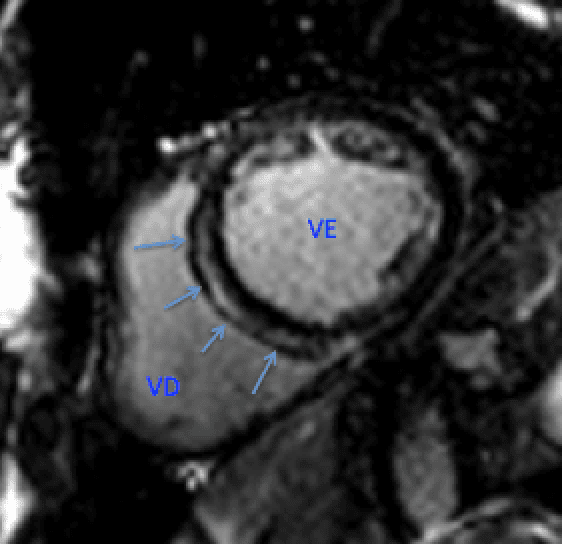

Já ouviu falar de disjunção anular mitral? Vamos ver o que você precisa saber. Começando com um caso:Paciente feminino, 22 anos, com extrassístoles ventriculares frequentes. Imagem mostra o seguinteO …